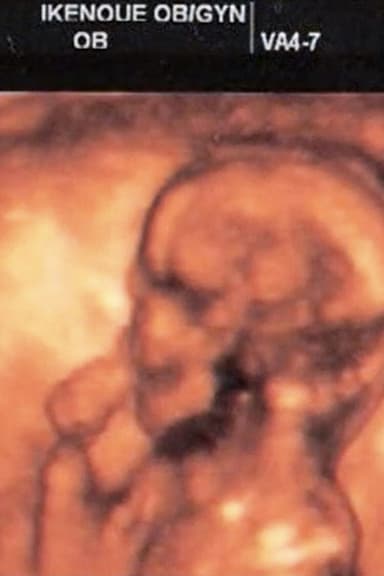

Born: 22nd October, 1981Age: 45Birthplace: Tokyo, Tokyo Prefecture, JapanBiography: Yuri Muraoka was born in Tokyo in 1981. Dropped out of the high school attached to Japan Women's University, graduated the 26th class of Image Forum Institute of the Moving Image. Continues to create moving images and photographic works of "self-portraiture". All of her works are self-created and self-performed. Mother of two children.